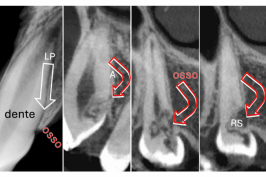

Onde está o dente que não apareceu na boca?